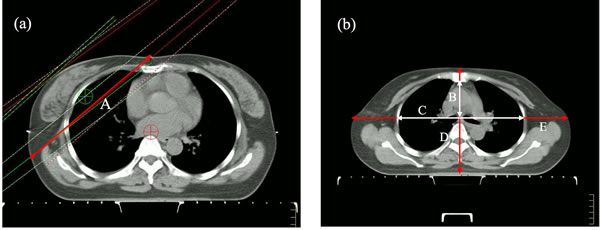

We collected body mass index (BMI) and breast CTV, breast shape, thorax index, body width, body depth on the simulation-localization-CT scans. The breast CTV was used as a surrogate for breast volume. The tangential fields-based breast separation was created to be a simple surrogate for breast shape. The breast separation was defined as the distance between the beam entrance points of medial and lateral tangential fields in the for-IMRT plan on the ISO plane. Thorax index was a parameter that reflected thorax shape, thorax index was defined as the chest width to depth ratio on the second rib inserted into the sternum plane. Chest depth was measured from the ventral surface of the vertebral body to the dorsal surface of the sternum on the midsternal line. Chest depth was measured between the inner surfaces of two symmetrical ribs, located perpendicularly to chest depth and divided in half at the widest point of the thoracic cage. Body width was defined as the distance between ventral and dorsal skin surface on the midsternal line. Body depth was defined as the distance between left and right skin surface on the extension of the chest depth line. The definitions of anatomic parameters are shown in Figure 2. The distance from upper border of tangential fields to humeral head was also measured.

Figure 2: Definition of anatomic parameters: A = breast separation (red), B = thorax depth (white), C = thorax width (white), D = body depth (red), E = body width (red).